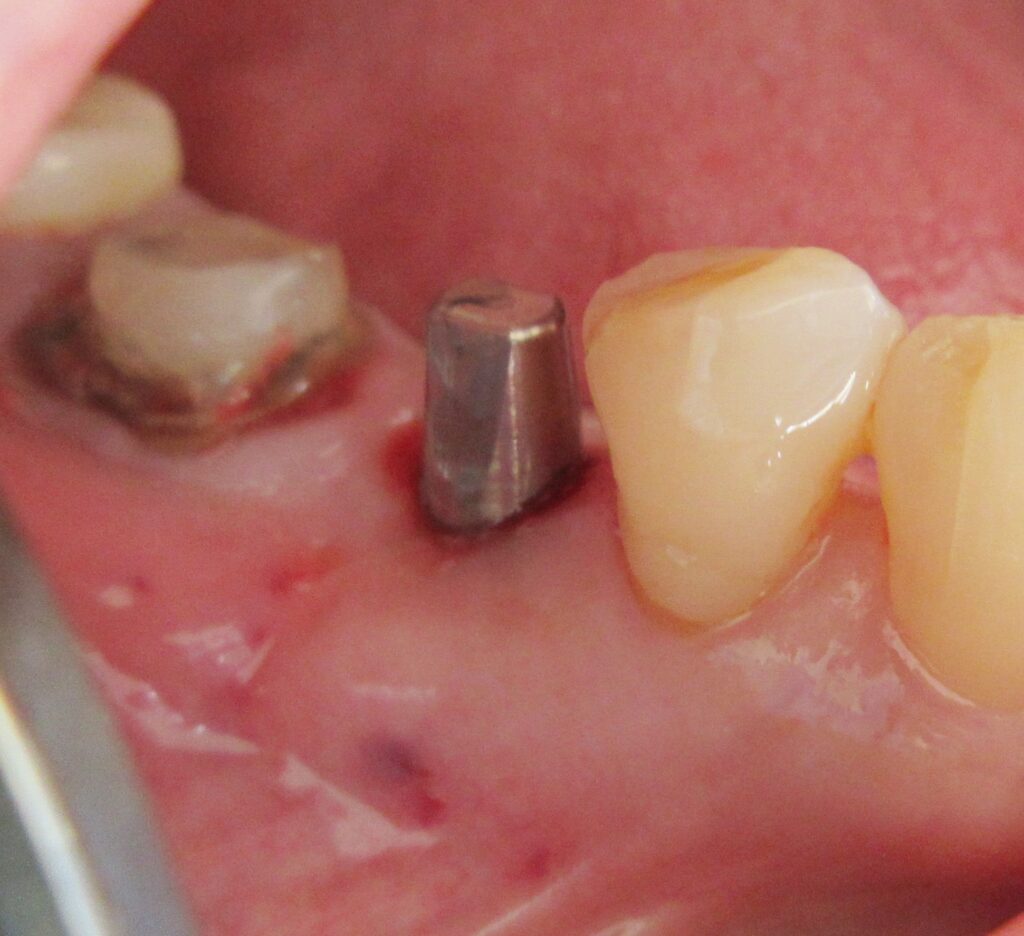

まずは歯茎から骨の部分までを穴開けパンチの要領で穴を開けていきます。

くりぬいた部分の歯肉を取り除き、次は骨に穴を開けていきます。

ドリルの先端を細い物から徐々に大きい物に変えながら、植立するインプラント体のネジの部分を除いた胴の部分の太さに合わせた大きさの穴を開けていきます。

開けた穴に、専用道具を使ってネジを締めるように長さ2センチ程のインプラントを骨に埋め込んでいきます。

しっかりとインプラント埋め込まれた後は、動揺がないか、噛んだ時に当たらないかなどを確認して、最後にパノラマ写真を撮影して今回のオペは終了となりました。